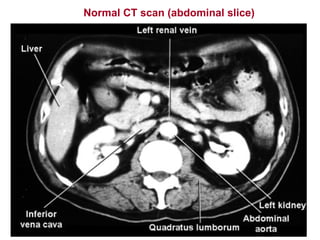

Normal CT scan (abdominal slice)

Normal CT scan(abdominal slice)